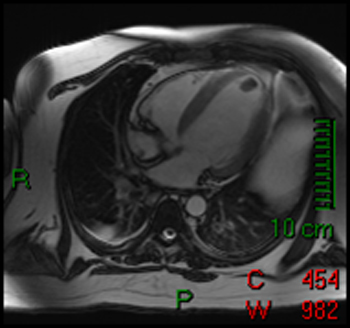

3) This horizontal long axis SSFP demonstrates which of the following entities?